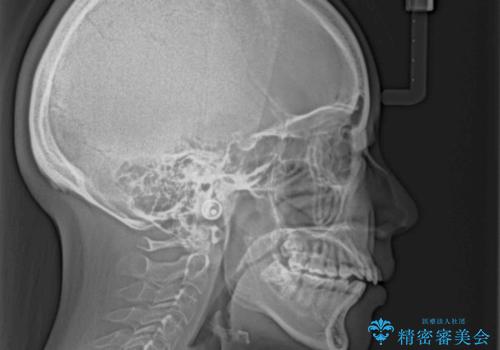

- 上下の前歯が非接触であることと、それに伴う口元の閉じにくさを気にして来院された患者様です。

奥歯の咬み合わせを見ると、上顎が下顎に対して相対的に前方にありました。

口元の閉じにくさを改善するためには、上顎臼歯を後方に移動させた咬み合わせにする必要があります。

インビザライン単体で改善することも可能ですが、達成する可能性が高くないため、カリエールディスタライザーという補助装置を併用して、より確実性を上げることとしました。

奥歯の咬み合わせを改善しながら、並行してインビザラインで歯列を整えることとしました。